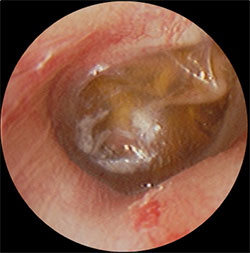

・鼓膜の内側に褐色の液体の貯留を認める

などの症状がでてきます。